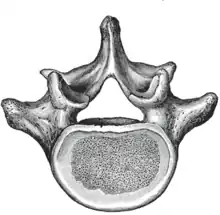

A typical lumbar vertebra

The adjacent figure depicts the general characteristics of the first through fourth lumbar vertebrae. The fifth vertebra contains certain peculiarities, which are detailed below.

As with other vertebrae, each lumbar vertebra consists of a vertebral body and a vertebral arch. The vertebral arch, consisting of a pair of pedicles and a pair of laminae, encloses the vertebral foramen (opening) and supports seven processes.

The vertebral foramen within the arch is triangular, larger than the thoracic vertebrae, but smaller than in the cervical vertebrae.[1]